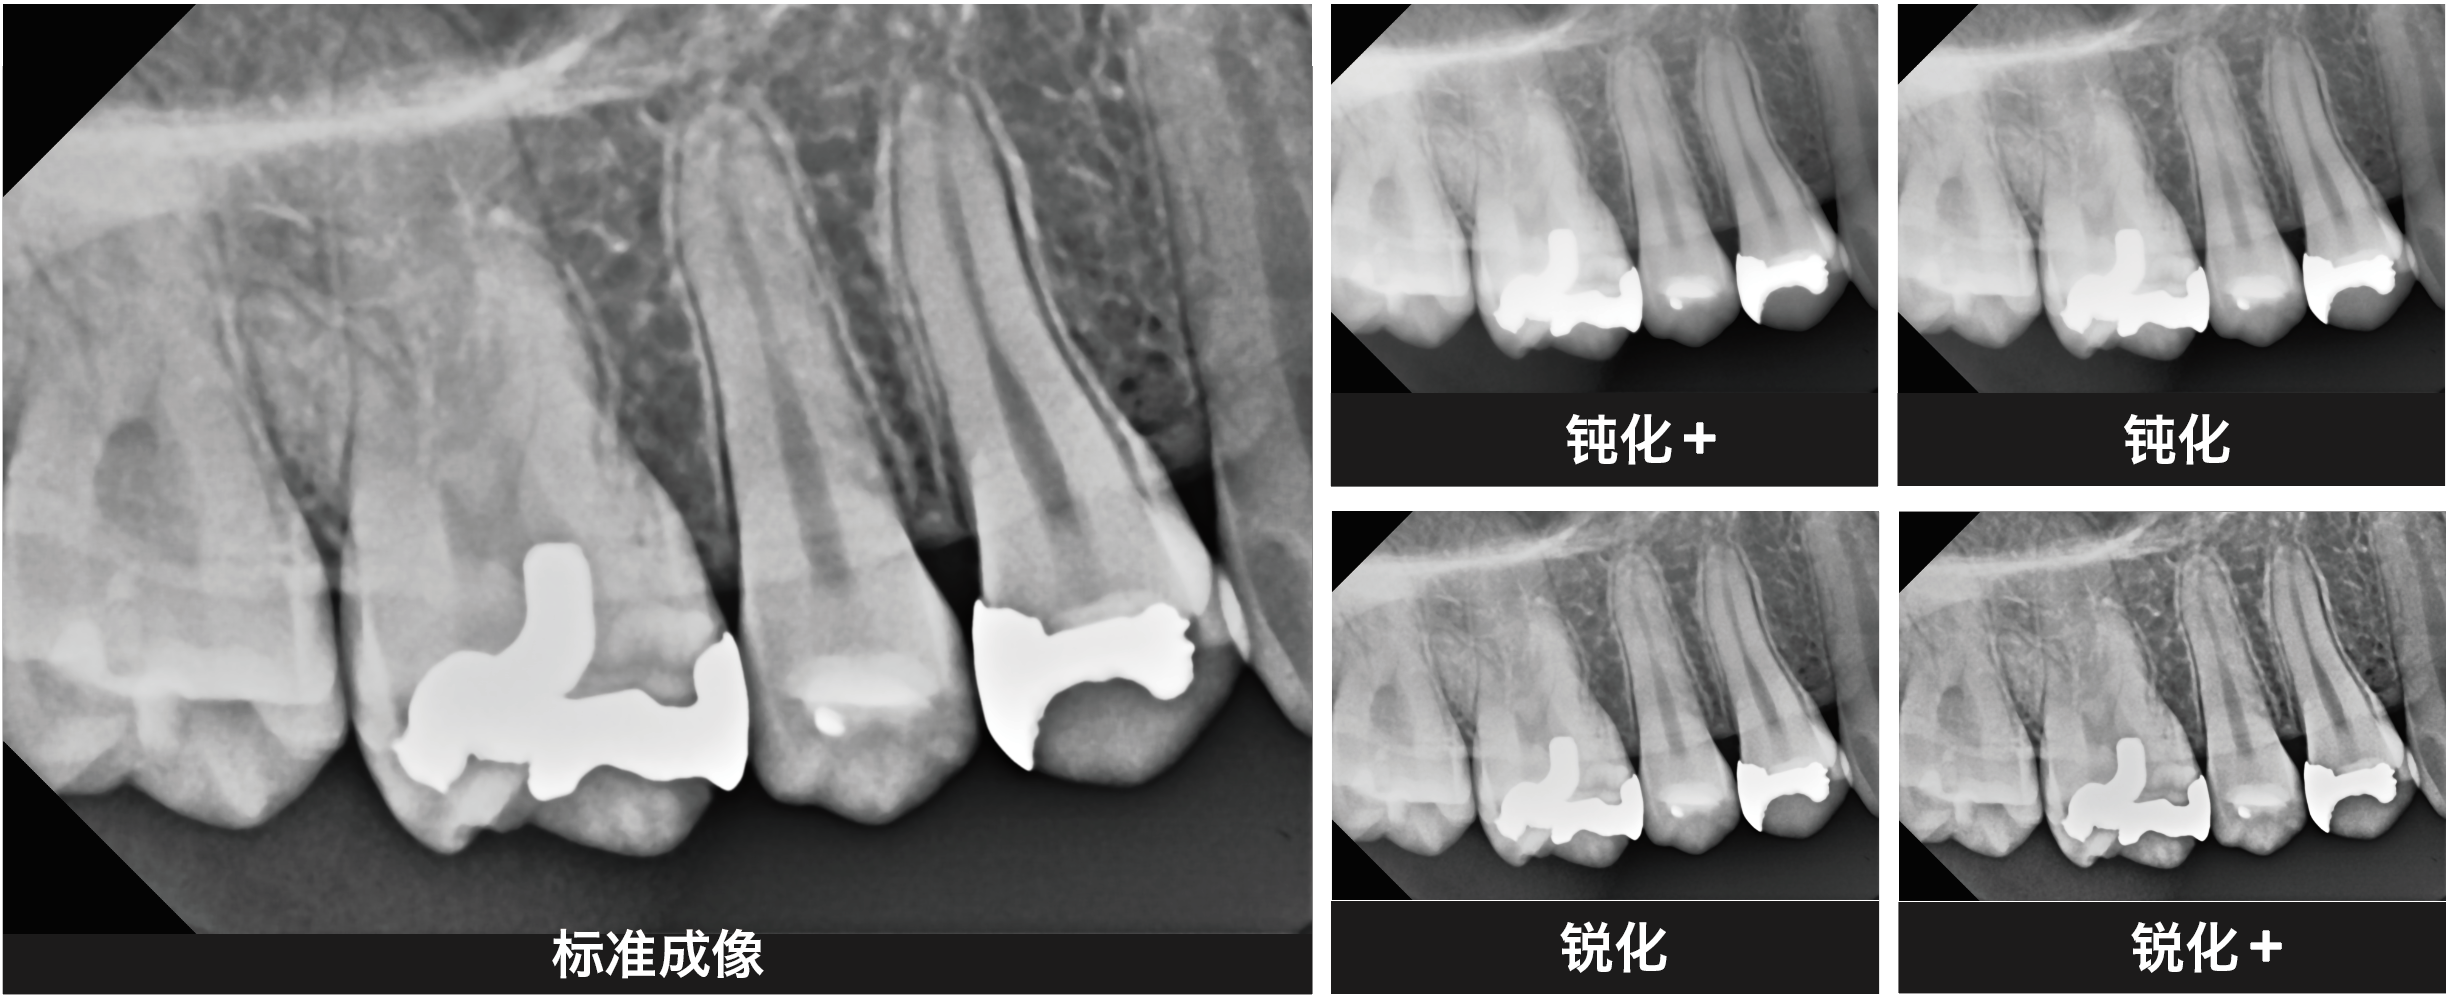

登騰口內(nèi)傳感器是一種獲取根尖周圖像以檢查口腔內(nèi)牙齒和組織的醫(yī)療設(shè)備,用戶(hù)可選擇共計(jì)五個(gè)級(jí)別的圖像過(guò)濾器以檢查采集的圖像。